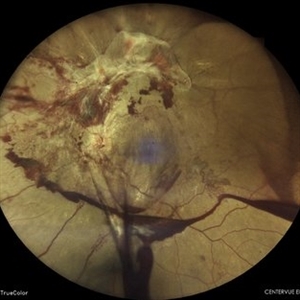

Giant Retinal Tear with Retina Detachment, Both Eyes

Fundus photograph of a 13 year-old female with giant retinal tear and retinal detachment in both eyes.

Photographer: Dr. Akansha Sharma-Retina Foundation, Ahmedabad

Condition/keywords: giant retinal tear, proliferative vitreoretinopathy (PVR)